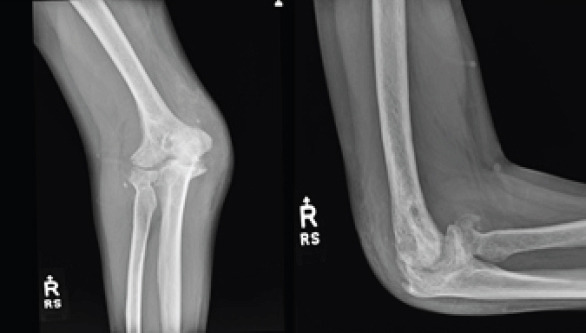

Case report: We report a case of a 50-year-old male who presented after the development of post-traumatic arthritis of the elbow after multiple prior surgeries. He was treated with an interpositional arthroplasty using an Achilles tendon graft and allowed immediate range of motion as tolerated in a hinged elbow brace without the use of any form of distraction external fixation. At his final follow-up, he has significantly improved pain, range of motion, and patient-reported Visual Analog Scale , American shoulder and elbow surgeons, mayo elbow performance score, and disabilities of the arm, shoulder and hand scores.